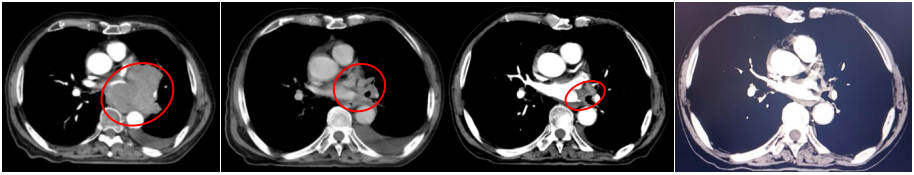

胸部增强CT(2022-05-23):1、左肺门占位(较大截面约7.8cm×8.3cm)伴纵隔多发肿大淋巴结、远端阻塞性肺炎、考虑中央型肺癌,累及左肺动脉及左心房、心室不除外。2、双肺肺气肿。3、左侧胸腔积液,累及左侧胸膜可能。4、心包少量积液。5、肝内多发小囊肿可能。

2022-07-19(2周期后)胸部、全腹部增强CT:1.肺癌复查,较前(2022-05-23)左肺门占位明显减小,左肺下叶远端阻塞性改变较前范围减小;2.双肺肺气肿;3.左侧胸腔积液,累及左侧胸膜可能,较前略增多;4.心包少量积液,较前增多;5.肝内多发囊肿;右肾上极小囊肿;6.肝左叶内小海绵状血管瘤可能;7.前列腺增大伴钙化。

2022-09-30(4周期后)胸部、全腹部增强CT:1.肺癌复查,较前(2022-07-19)左肺门占位减小,左肺下叶远端阻塞性改变较前范围减小;2.双肺肺气肿;3.左侧胸腔积液,累及左侧胸膜可能,较前减少;4.心包少量积液,大致同前;5.肝内多发囊肿;右肾上级小囊肿;6.肝左叶内小海绵状血管瘤可能;7.前列腺增大伴钙化。

2022-11-21(6周期后)胸部、全腹部增强CT:左肺门占位较前(2022-09-30)减小,左肺下叶远端阻塞性改变较前变化不大;左侧胸腔积液,累及左侧胸膜可能,较前减少;心包少量积液,大致同前。

疗效评估:PR(接近CR)。